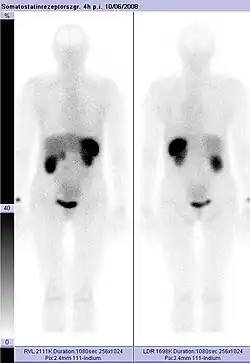

Somatostatin-Rezeptor-Szintigrafie

Normale Aktivität in Leber, Galle, Milz, Nieren und Harnblase

Unmittelbar vor der Injektion wird das Konjugat Komplexbildner–Somatostatin-Analogon mit dem Radioisotop, meist 111Indium, beladen. Die freien Indiumionen werden durch den Komplexbildner vollständig chelatisiert. Das so hergestellte Radiopharmakon wird intravenös appliziert und verteilt sich dabei im Blutkreislauf des Patienten. An Zellen, die entsprechende Somatostatin-Rezeptoren besitzen, reichert sich das Radiopharmakon an. Dies sind unter anderem der Hypothalamus, die Großhirnrinde und der Hirnstamm, sowie eine Reihe von Tumoren und deren Metastasen. Etwa vier Stunden nach der Verabreichung des Radiopharmakons wird eine erste Aufnahme durchgeführt. Die Dauer beträgt etwa eine Stunde. Das angereicherte Radiopharmakon zerfällt. Die dabei abgestrahlte Gammastrahlung durchdringt das umgebende Gewebe und wird mittels einer Gammakamera detektiert und per Bildverarbeitung zu einem Bild zusammengesetzt. Die Anzahl der Zerfallsereignisse ist in den Bereichen der Anreicherung besonders hoch. Am nächsten Tag wird meist eine zweite Szintigrafie durchgeführt (siehe auch: Szintigrafie und Single Photon Emission Computed Tomography).